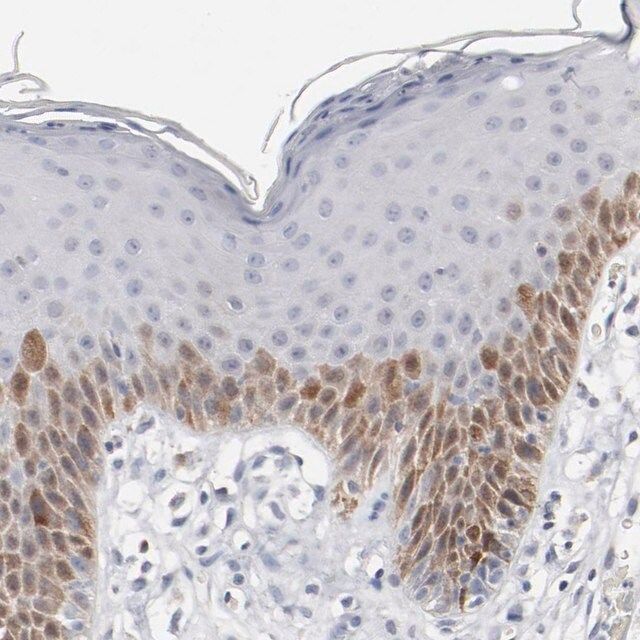

Anti-CDK1 antibody produced in rabbit, a Prestige Antibody, is developed and validated by the Human Protein Atlas (HPA) project (www.proteinatlas.org). Each antibody is tested by immunohistochemistry against hundreds of normal and disease tissues. These images can be viewed on the Human Protein Atlas (HPA) site by clicking on the Image Gallery link. The antibodies are also tested using immunofluorescence and western blotting. To view these protocols and other useful information about Prestige Antibodies and the HPA, visit sigma.com/prestige.

- IHC tissue array of 44 normal human tissues and 20 of the most common cancer type tissues.